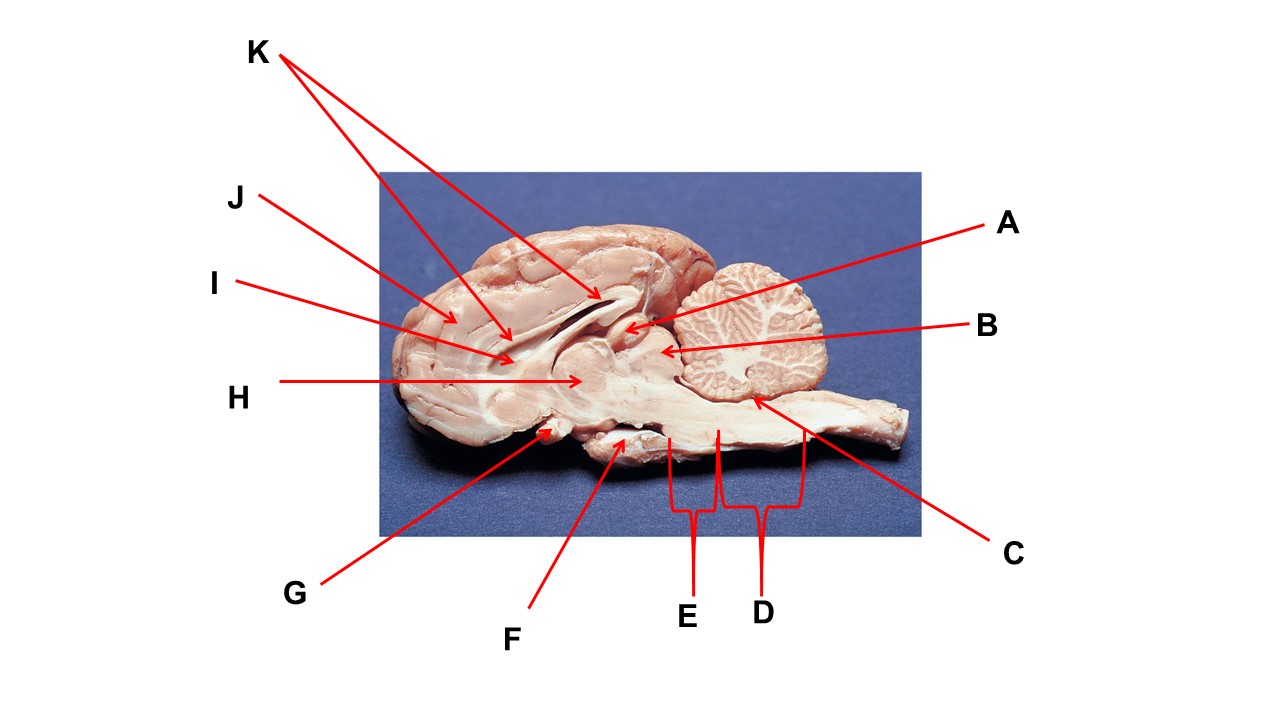

Name the structure at the tip of arrow K.

ventral root

Name the structure at the tip of arrow A.

pineal gland

The cavity at the tip of arrow I is the _____.

lateral ventricular

The cavity at the tip of arrow I is filled with ______.

cerebrospinal fluid

Name the structure at the tip of arrow F

mammillary body

Name the structure at the tip of arrow A.

pineal gland

Name the structure at the tip of arrow G

optic chiasma

Name the nerve at the tip of arrow H.

optic